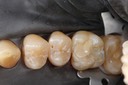

Larry Fujioka #11 - 12 finish

Larry Fujioka #11-12 finish

Larry Fujioka #11,12 finish buccal